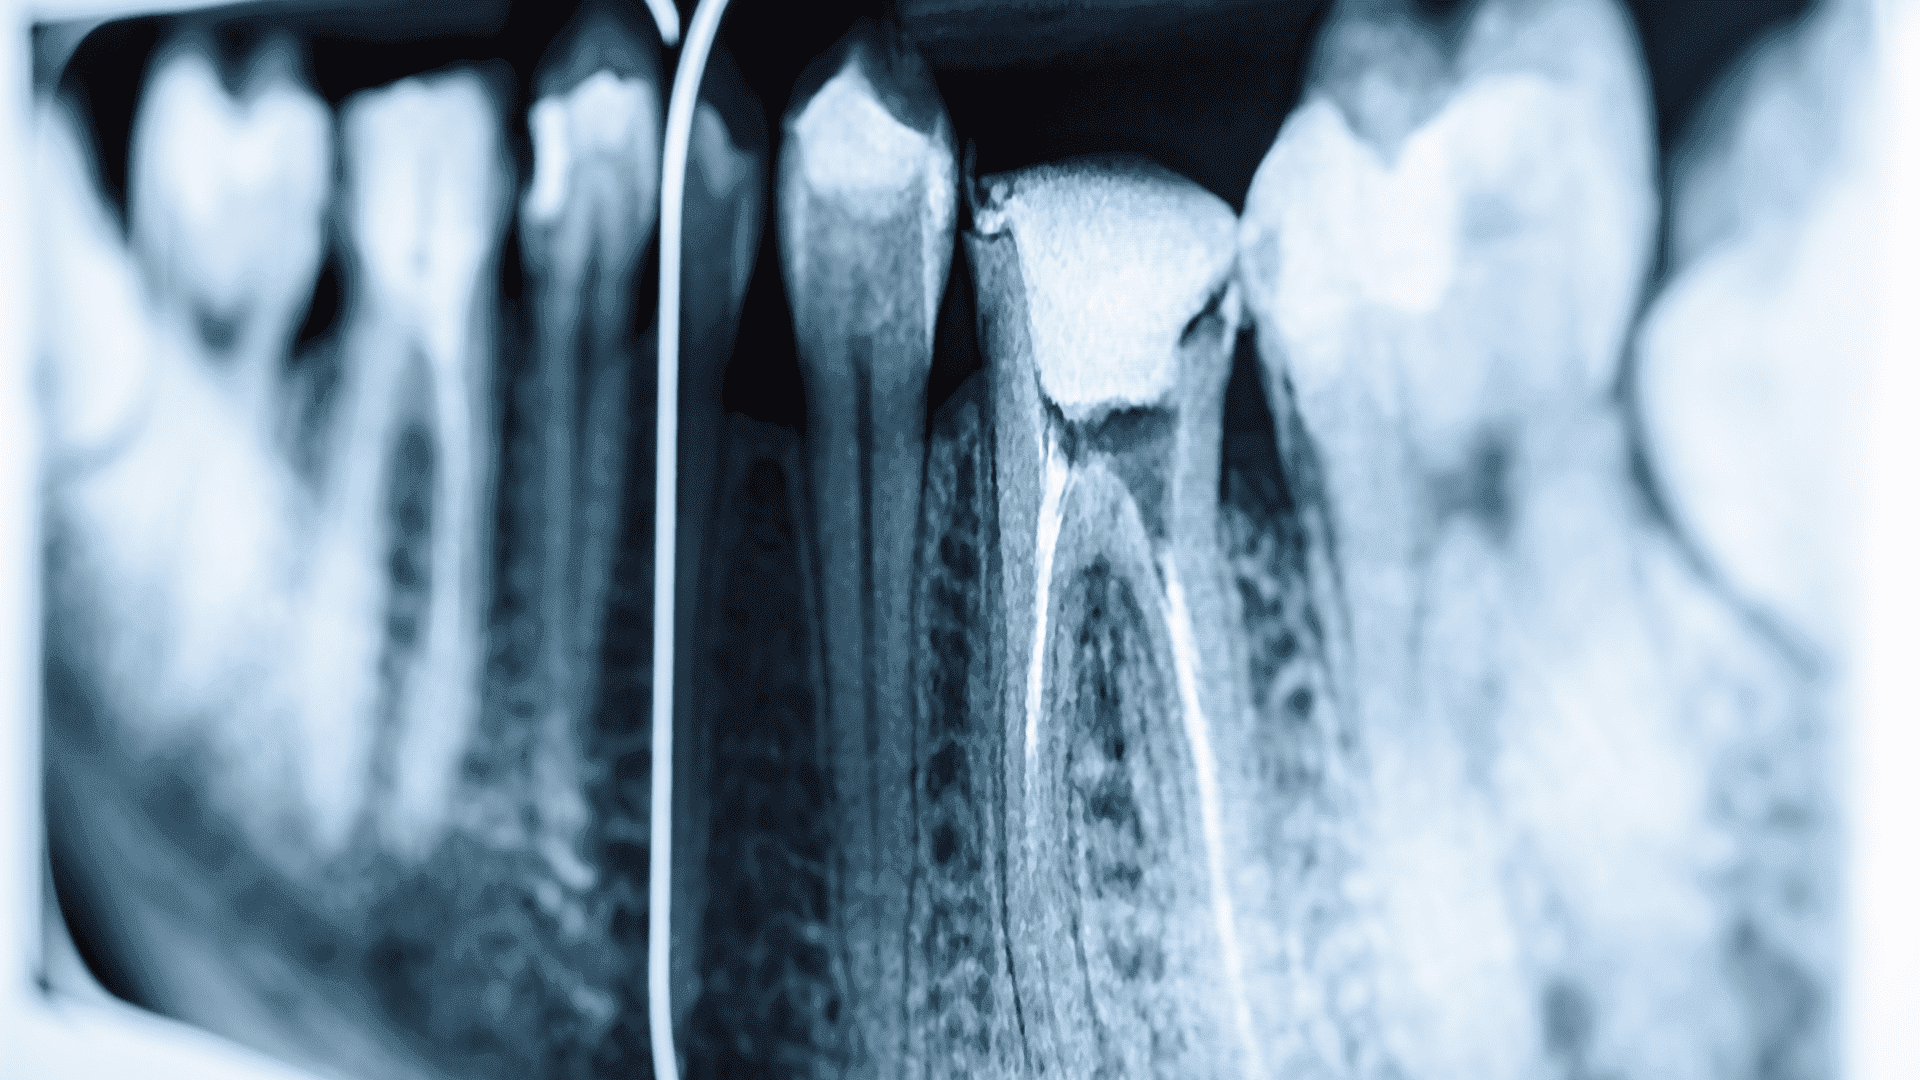

Zdjęcie punktowe RTG stanowi fundament nowoczesnej diagnostyki stomatologicznej, umożliwiając szczegółową ocenę stanu zdrowia zębów i tkanki kostnej szczęki oraz żuchwy. Ta technika radiologiczna skupia się na konkretnym obszarze zainteresowania, dostarczając obraz o wysokiej rozdzielczości, co jest nieocenione w precyzyjnym planowaniu leczenia. Od identyfikacji próchnicy po zaawansowane diagnozy chorób periodontologicznych i endodontycznych - zdjęcia punktowe RTG są niezbędnym narzędziem w rękach każdego dentysty. Ich niskie dawki promieniowania oraz szybkość wykonania sprawiają, że są one zarówno bezpieczne, jak i wygodne dla pacjentów.

Zdjęcia punktowe RTG wykorzystują zaawansowaną technologię radiologiczną do generowania szczegółowych obrazów pojedynczych zębów i ich bezpośredniego otoczenia. Dzięki zastosowaniu specjalistycznych aparatur RTG, które koncentrują wiązkę promieni na bardzo małym obszarze, możliwe jest uzyskanie wyraźnych i dokładnych obrazów, przy znacznie niższej dawce promieniowania w porównaniu do tradycyjnych metod radiologicznych. Nowoczesne urządzenia do RTG punktowego są również wyposażone w cyfrowe systemy przetwarzania obrazu, co pozwala na natychmiastowy podgląd wyników i ich łatwą archiwizację w cyfrowej dokumentacji pacjenta.

Zabieg wykonania zdjęcia punktowego RTG jest szybki, bezbolesny i nie wymaga specjalnego przygotowania. Pacjent zostaje poproszony o umieszczenie małej płytki RTG w ustach, w pobliżu obszaru, który ma zostać zbadany. Następnie technik lub dentysta pozycjonuje urządzenie RTG tak, aby skierować wiązkę promieni na interesujący obszar. Cały proces trwa zaledwie kilka sekund, a uzyskane obrazy są od razu dostępne do analizy. Dzięki minimalnej dawce promieniowania i szybkości wykonania, zdjęcia punktowe RTG są uznawane za jedną z najbezpieczniejszych metod diagnostycznych w stomatologii, pozwalając na szybką i skuteczną ocenę stanu zdrowia zębów pacjenta.